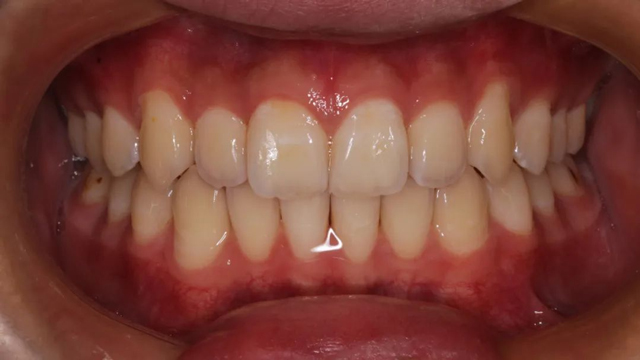

2024年9月(矫正结束后口内照)

该病例的治疗周期长达三年,跨替牙期和年轻恒牙期。治疗结束时,小患者收获了一口整齐美观的牙齿,也从满脸稚气的孩童长成了青葱少年。

“隐形矫正一般2-3月复诊一次,从节约时间来说很受家长青睐,但前提是小朋友要有很好的依从性,这是获得满意效果的前提。案例中的这个小朋友和家长与医生的配合度非常高,这也是我们能治疗成功的必要因素。”